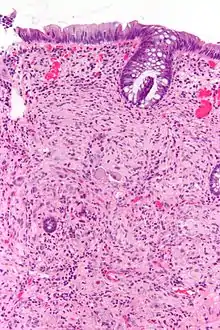

Pathologiquement, les ganglioneuromes sont composés de cellules ganglionnaires, de cellules de Schwann et de tissu fibreux[4]. Les ganglioneuromes sont des tumeurs solides et fermes, généralement de couleur blanche à l'œil nu.